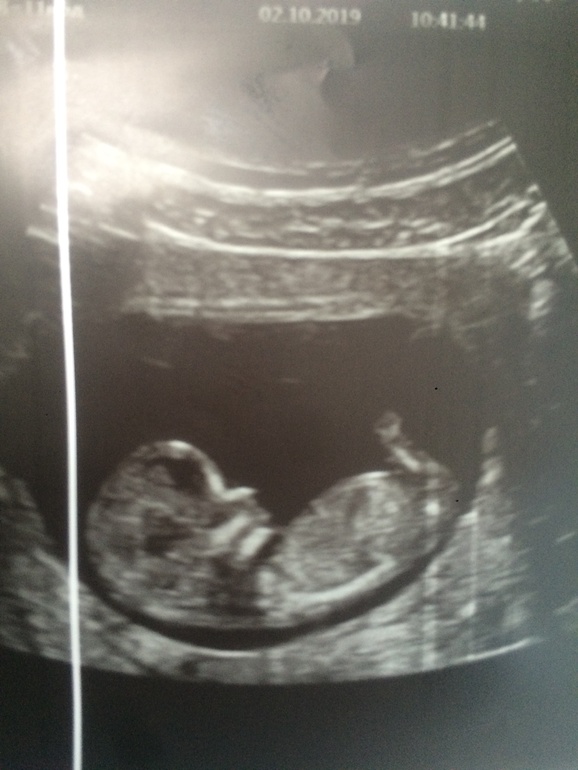

Вот и дождалась) сходили на скрининг. Тряслась и переживала что-то сильно) по узи все в норме. Ктр 51, сердечко ритмичное, всё на месте, лежит, лапками дрыгает мой малыш 🙃🥰

Пол вот только не сказали 🤷♀️ Кровь ещё сдала, будет через 7 дней.